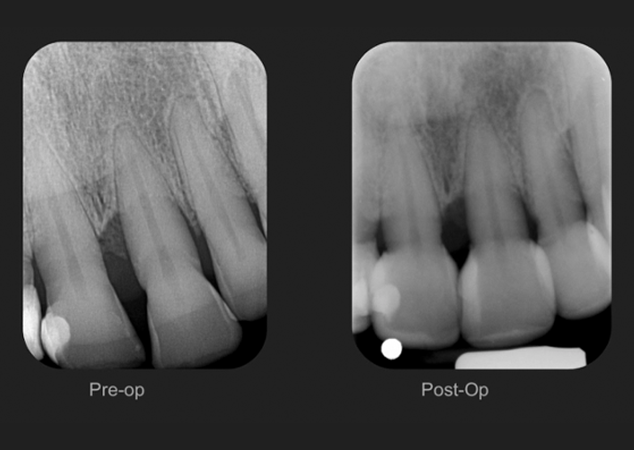

FIG. 10

Radiographies périapicales pré et post-opératoires.

Une fois la digue en caoutchouc retirée, les embrasures incisives sont réexaminées pour une mise en forme finale. Des radiographies périapicales postopératoires sont prises pour confirmer l'absence d'excès de restauration sous-gingival (Fig. 10). Remarquez les courbes généreuses obtenues grâce au contour anatomique des matrices pour triangles noirs Bioclear. (Fig. 11)